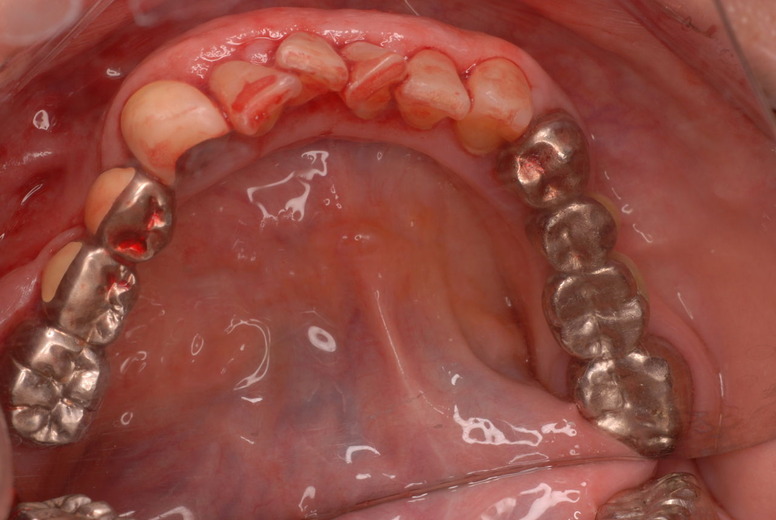

入れ歯の話から入りました。色々不満で注文があるようです。でも話が一段落して口腔内を調べると殆どの歯が重症で抜けそうな歯だらけなのです。

ご自分でやられても歯茎から血が出ないと話をされていましたが、私がブラシを当てると悲惨な状態であることがわかりました。